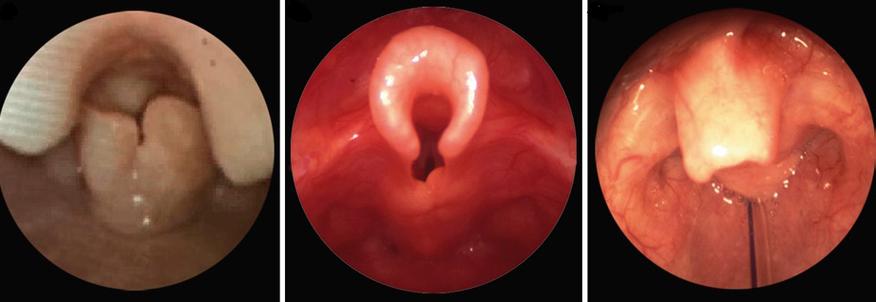

喉骨软化,也称为先天性喉喘鸣,是新生儿和婴儿时期一种非常常见的疾病,它的根本原因是婴儿喉部的软骨(主要是会厌软骨和杓状软骨)发育不够成熟、质地较软,导致在呼吸时,这些软化的软骨会向内塌陷,部分阻塞了上呼吸道,从而在吸气时产生特殊的声音。